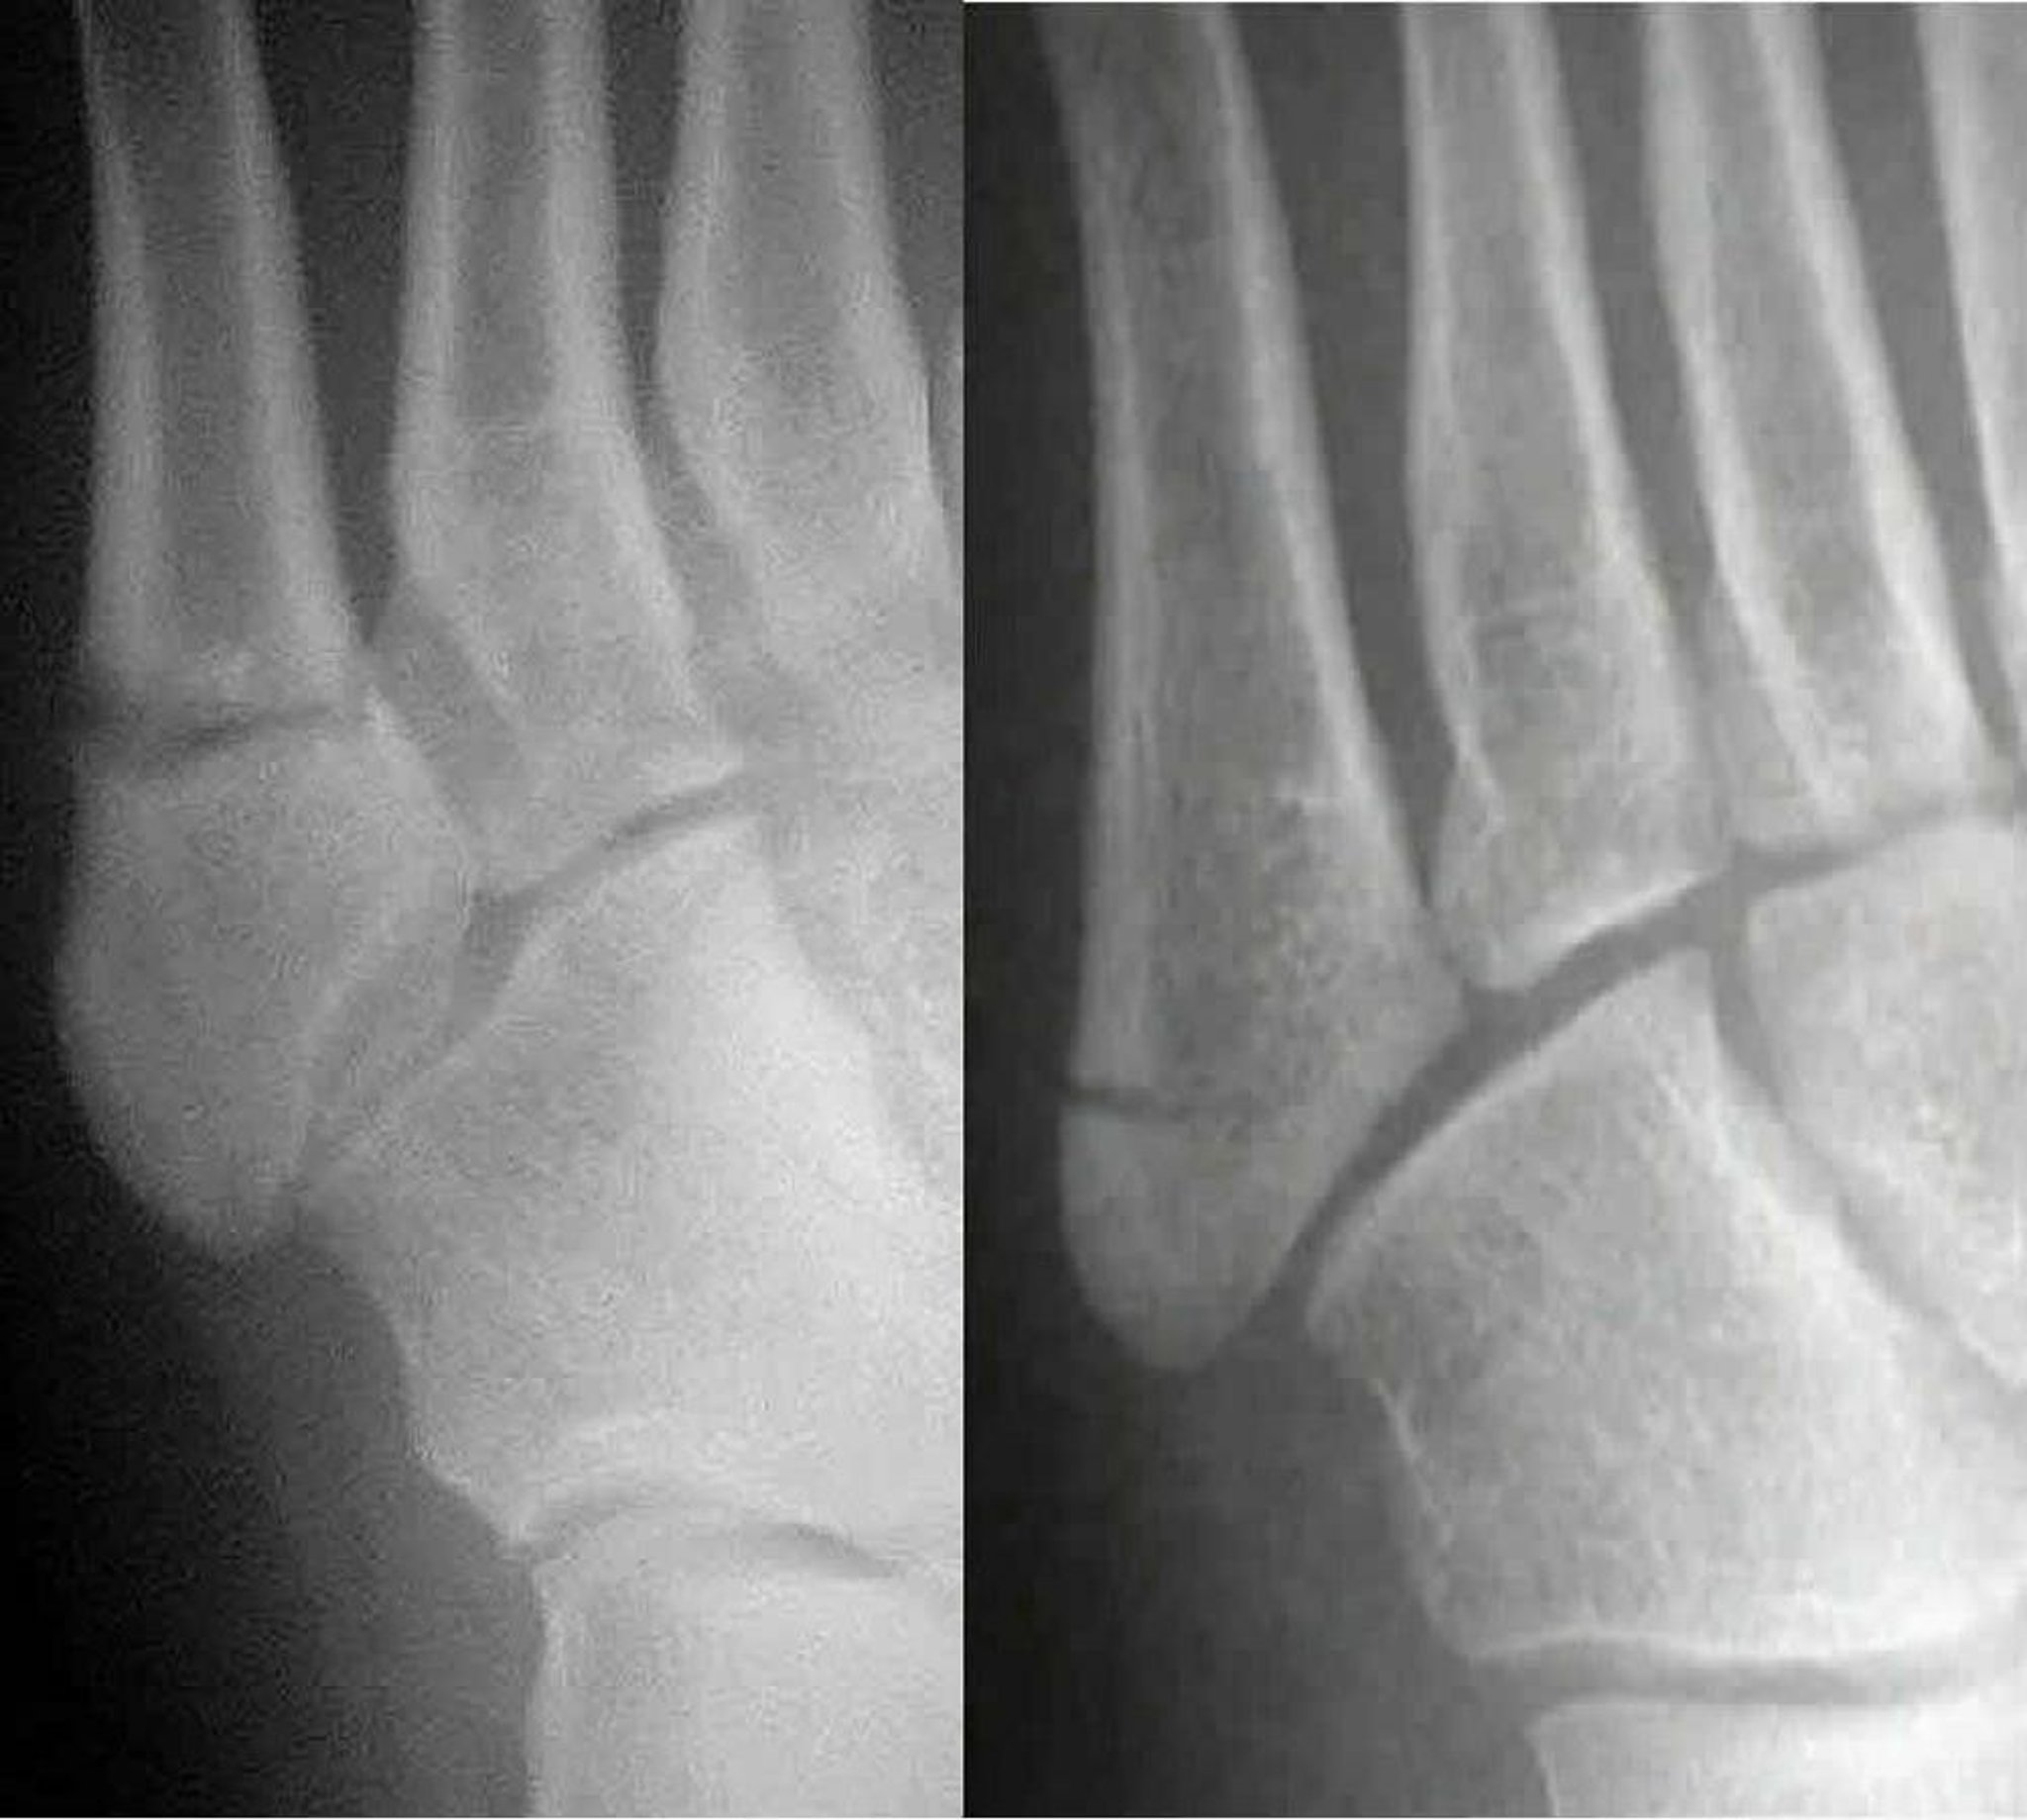

Jones vs Pseudo-Jones Fractures

A Jones fracture (left) involves the 5th metatarsal shaft; a pseudo-Jones fracture (right) involves the 5th metatarsal base. Distinguishing the two is important because they are treated differently.

Images courtesy of Danielle Campagne, MD.